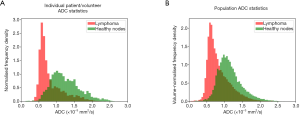

Table 2 shows the performance of the significant gADC discriminators. The order of the diagnostic accuracies of gADC parameters by AUC performance from highest to lowest was: 10th centile, mean, median, 90th centile, skewness and kurtosis. Figure 2 visualises the overlap of gADC parameters between lymphoma and healthy individuals. There was no significant difference of AUC between mean and median gADC, 10th and 90th centile gADC (each P>0.131). Mean gADC AUC was significantly larger than gADC skewness AUC (P=0.032) and gADC kurtosis (P=0.004). 10th centile and median gADC AUC were significantly larger than for gADC kurtosis (each P<0.010). Median and 90th centile gADC AUC were significantly larger than for gADC skewness (each P<0.043). In correspondence to the AUC, the highest Youden index among gADC histogram parameters was calculated for the 10th centile gADC at a threshold of 0.67×10−3 mm2/s, smaller values identifying disease with 91% sensitivity and 95% specificity. A median gADC value less than 0.91×10−3 mm2/s identified disease with 87% sensitivity and 95% specificity. 81% sensitivity and 95% specificity was shown for a threshold mean ADC value of 0.95×10−3 mm2/s. Sensitivity of the 10th centile cut-off was significantly larger than for the mean gADC cut-off (P=0.046). Exemplar maximum intensity projections delineating lymph nodes of a lymphoma patient and a healthy volunteer are demonstrated in Figure 3. Figure 4 visualises the corresponding gADC histograms of lymphoma and healthy nodes of this particular patient (A) as well as the ADC distribution across all study subjects in both groups (B). No gADC parameter showed significant difference between different lymphoma subtypes (each P>0.324).

In total 307 diseased nodal volumes were identified in the lymphoma patients and 1,002 healthy individual nodes were identified in the volunteer group by the connected component labelling algorithm. Table 3 shows the diagnostic performance of the ADC parameters derived from distinct nodal volumes, which differed significantly between the two groups. In contrast to the corresponding gADC parameters, distinct nodal min and max ADC were significantly lower in lymphoma. The order of diagnostic accuracies of the parameters as indicated by the AUC from highest to lowest was: median and 10th centile, mean, min, 90th centile, skewness, kurtosis and max ADC. Violin plots demonstrating the distribution of parameters calculated for individual diseased/healthy distinct nodal volumes are compared in Figure 5. The natural logarithm of nodal volume, ln(tDV), showed the highest Youden index—a threshold of 0.08 (representing a 1.08 mL nodal volume), resulting in 75% sensitivity and 91% specificity.